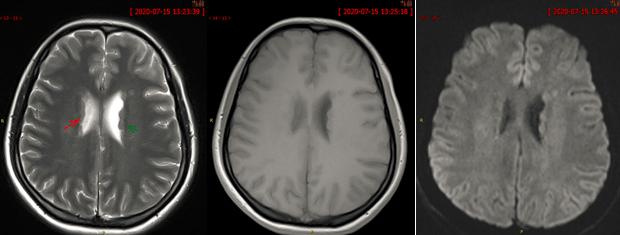

脑灰质异位,脑灰质异位图片

结果:灰质异位(gmh).

精品课件脑灰质异位症的影像诊断

医影学堂丨八个病例带你看懂脑灰质异位的三种类型